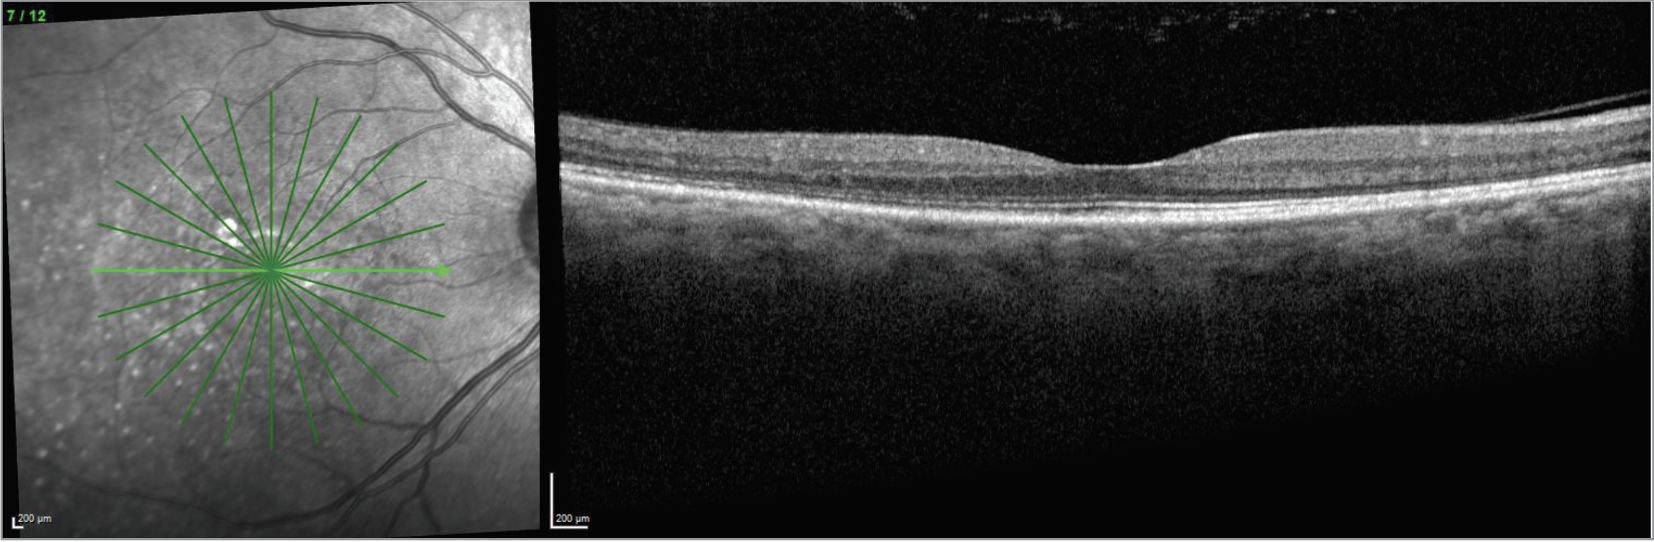

| CaptionFigure 7. OCT of the right eye one year after stopping infliximab. |

| Figure 8. OCT of the left eye one year after stopping infliximab. |

One week after pulse-dose steroids and starting infliximab, the bacillary detachments had completely resolved in both eyes, with improvement of visual acuity to 20/80 in the right eye and 20/70 in the left eye.

The patient has now remained stable for one year after stopping infliximab, and her visual acuity has improved to 20/20 in both eyes.